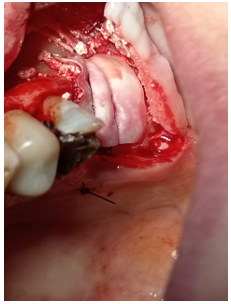

The lateral wall of the maxillary sinus was subsequently fenestrated with a special design blind osteotome, by gentle tapping with a hammer will break the margin of thin wall leaving bone shield attached to the sinus membrane (figure 5). The sinus membrane was raised and the mobilized part of the thin lateral sinus wall, together with the raised sinus membrane, was rotated medially and upwards (figure 6).

Figure 5: Lateral maxillary wall fenestration is achieved using a blind osteotome with gentle tapping, freeing the bony margins and leaving a thin bone shield attached to the sinus membrane

Figure 6: The sinus membrane is lifted upward and medially (A&B), with the thin bone shield still attached. The membrane remains intact without perforation and moves freely